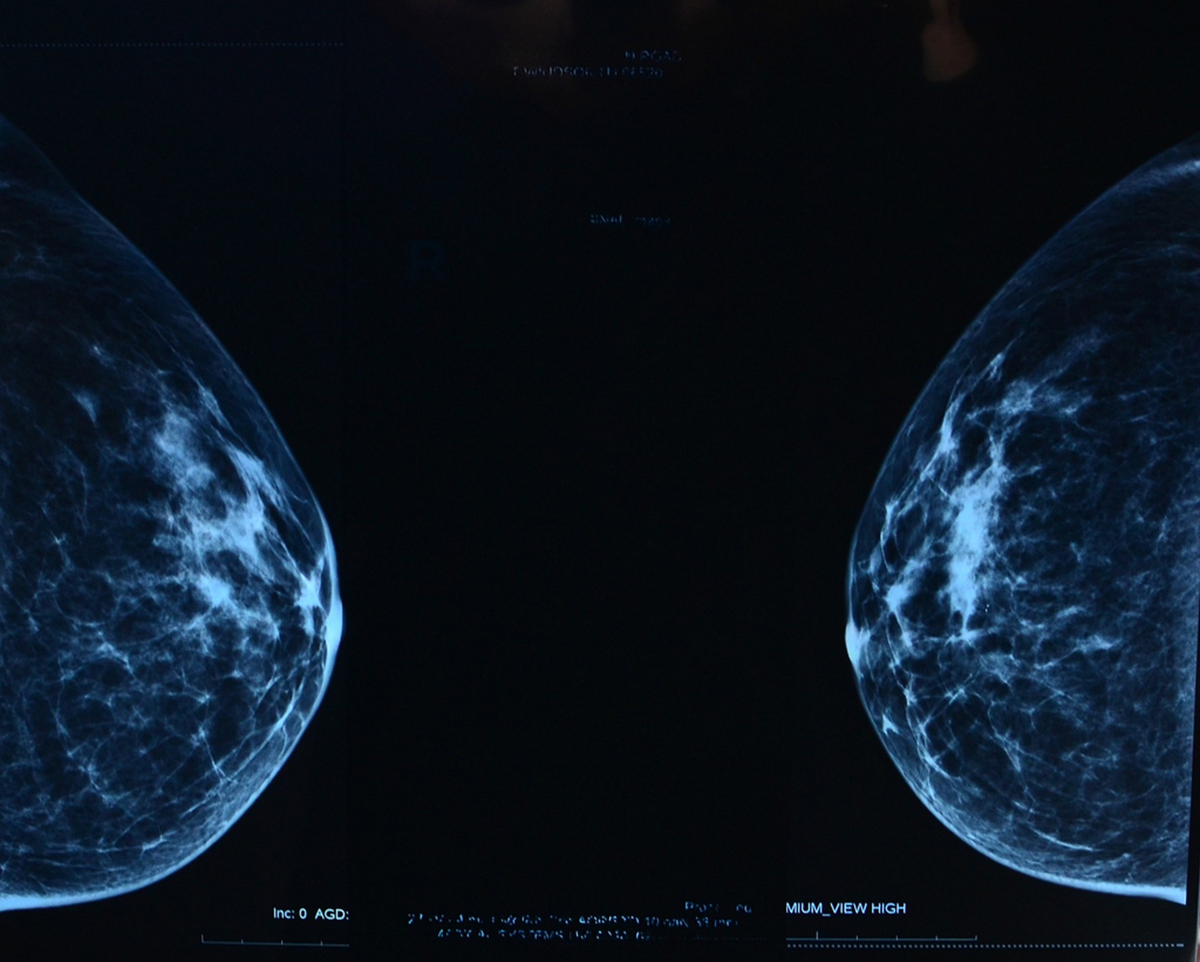

Mammograms can be digital or film. The actual picture looks different depending on which method is used, but both detect the exact same things. The pictures of your breasts are interpreted by a doctor — usually a radiologist — and you will get your results within a few weeks.